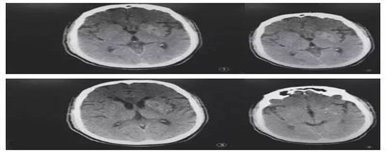

(3)影像学检查症状肢体对侧尾状核及豆状核MRI T1高信号,CT稍高密度。也有些患者虽然出现舞蹈症症状,但无影像学异常。